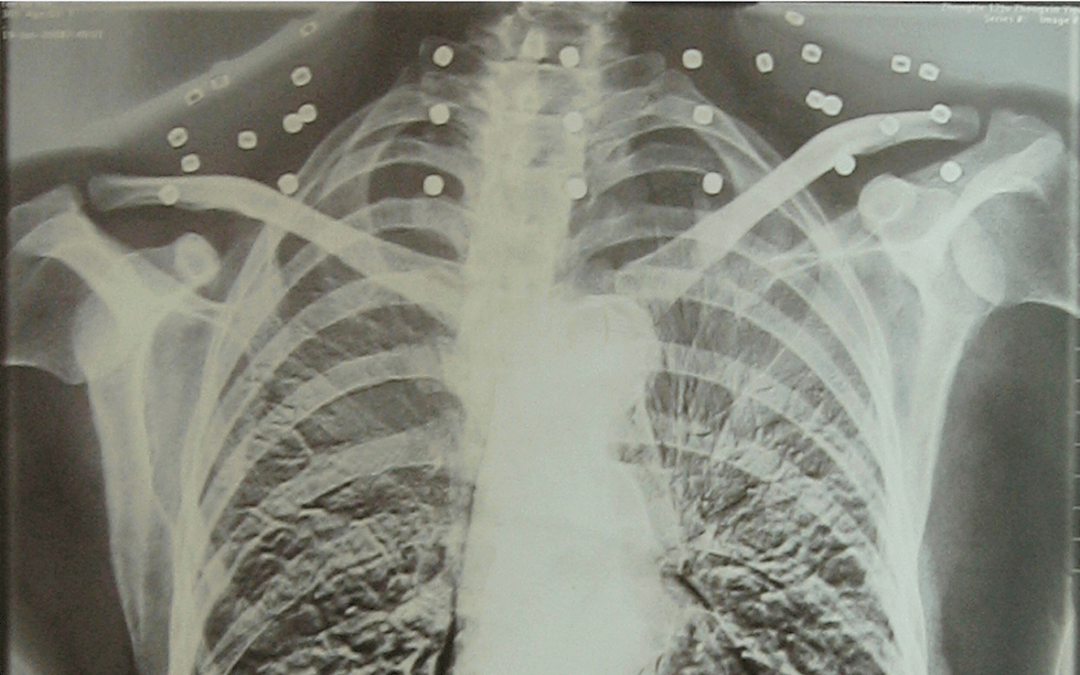

“老先生 您要把项链取下来再做CT” “我从来没戴过项链 你看会不会是弹片?” 这张照片 是今年82岁的吴以先老人 拍摄的一张CT照 20年前 吴以先在一次做...